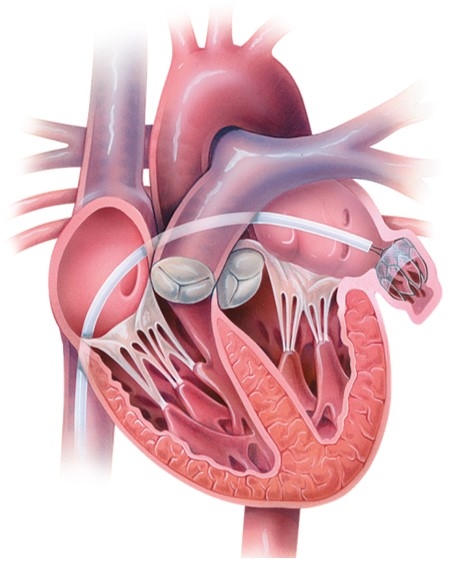

3.経皮的僧帽弁クリップ術

僧帽弁閉鎖不全症に対する治療は、外科的な開心術が基本戦略となります。ただし、外科的手術が困難な御高齢な方、低心機能の方、心臓外科手術後の方などに対する治療として、経皮的僧帽弁クリップ術というカテーテル手術が考案されました。

4.経皮的僧帽弁クリップ術の実際

経皮的僧帽弁クリップ術はカテーテルを用いて僧帽弁の前尖と後尖を繋ぎ合わせることにより、逆流を減少させる治療です。治療は全身麻酔下に行われ、心臓超音波専門医による経食道心エコーを頼りに治療を行っていきます。足の付け根(静脈)からカテーテルを挿入し、右心房から心房中隔を通って左心房にカテーテルを進めます。ガイドカテーテルからクリップのついたデリバリーシステムを僧帽弁の適切な位置まで持っていき、クリップを留置します。逆流が残存している場合は、クリップを置き直すことや、追加のクリップを留置することも可能です。クリップを留置し終えたら、足の付け根の止血を行い治療が終了します。通常は術後数日で退院することができます。